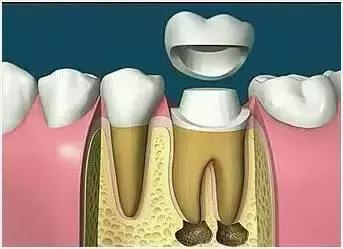

因牙体缺损过多,导致牙的强度(承受力量的性能)大幅度下降,不能很好地承受咀嚼力量。打桩的目的是增加牙根及牙冠的强度,增加患牙的稳固。

8、完成牙体修复

X线片显示根管充填完好,行暂时或永久牙体修复,带上牙冠,保护患牙。至此根管治疗才可算完成,同时根管治疗后还需复诊,一般周期可为3个月、半年、1年、2年或更长。